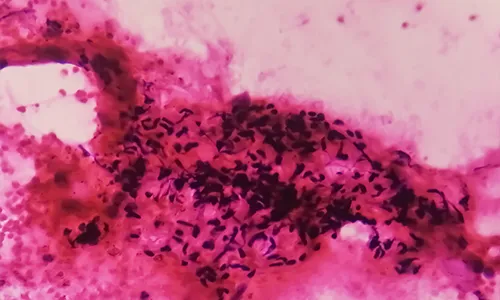

- Endometrial Biopsy